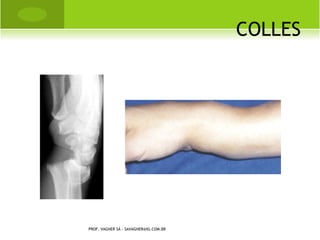

C OLLES

PROF. VAGNER SÁ - SAVAGNER@IG.COM.BR